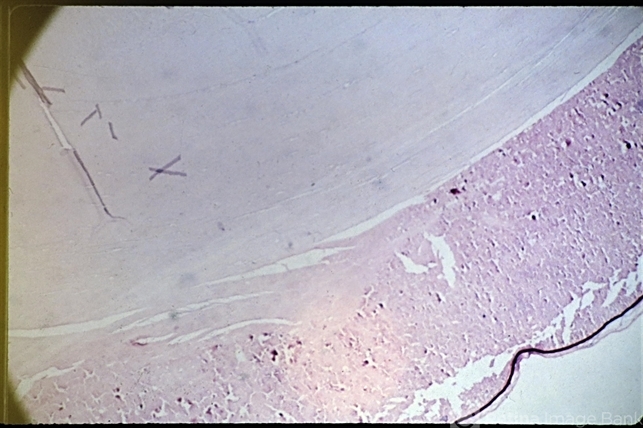

- Senile cataract (PAS x 16). Section shows liquefaction of the cortex under a deeply staining posterior capsule and a dense, lighter staining nuclear sclerosis. (Scheie Eye Institute, No. 4042.)